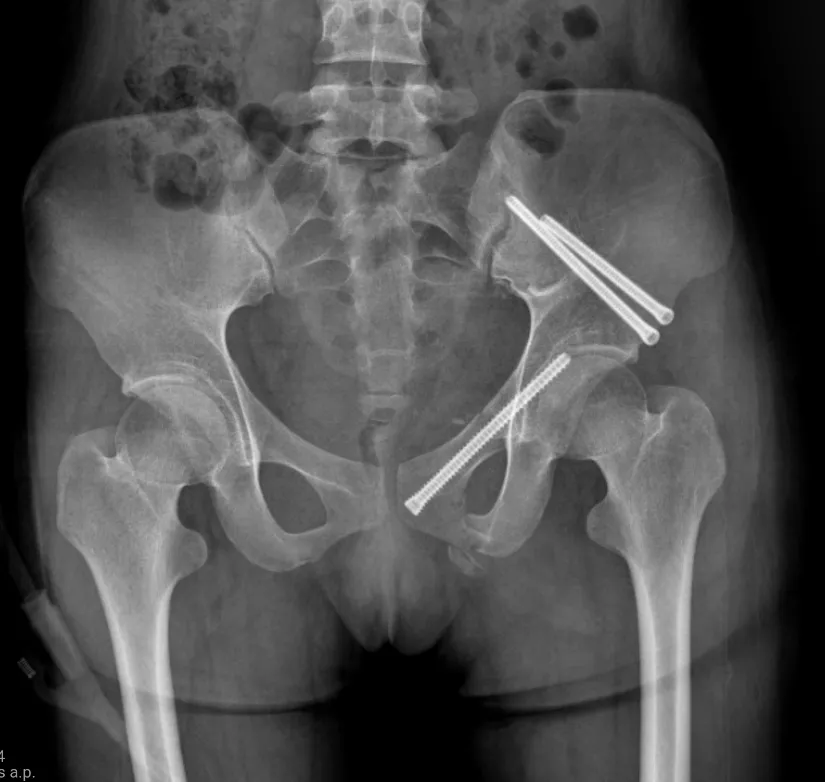

得知可以手術(shù),小陳又有了新的疑慮,切口會(huì)不會(huì)很大,疤痕是不是很明顯。但這些也早已在團(tuán)隊(duì)的預(yù)設(shè)之中,經(jīng)過談話解釋,逐一打消了她的疑慮。手術(shù)在小陳入院一周后順利完成。術(shù)后,身上的痛感逐日消退,當(dāng)換藥時(shí)瞥到微創(chuàng)切口,心情也好了起來,也越發(fā)配合創(chuàng)傷骨科團(tuán)隊(duì)的治療。經(jīng)過一段時(shí)間治療及護(hù)理,小陳能夠穿戴護(hù)腰坐起,重新找回了笑臉,并詢問主管醫(yī)生潘卓爾自己是否能出院了。經(jīng)過團(tuán)隊(duì)評(píng)估,小陳能夠出院了。

術(shù)后X光片(下)

針對(duì)小陳這樣的案例,使用的經(jīng)皮恥骨支螺釘內(nèi)固定術(shù)是一種髓內(nèi)固定技術(shù),在治療骨盆前環(huán)損傷中得到了越來越廣泛的應(yīng)用,常用于恥骨上支骨折和髖臼前柱骨折。經(jīng)過實(shí)踐分析,這是治療單側(cè)恥骨骨折的最佳治療方式,具有手術(shù)創(chuàng)傷小、術(shù)中出血量少、固定強(qiáng)度大、并發(fā)癥少及功能恢復(fù)快等優(yōu)點(diǎn)。